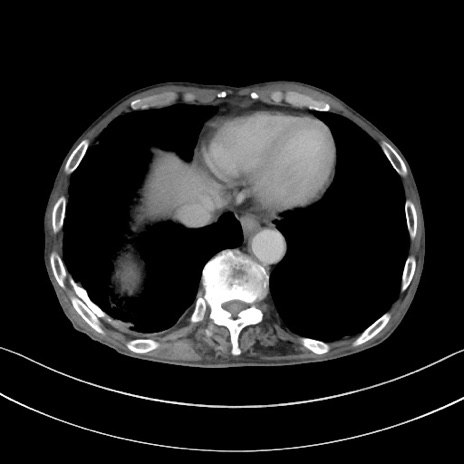

冠状断像

矢状断像